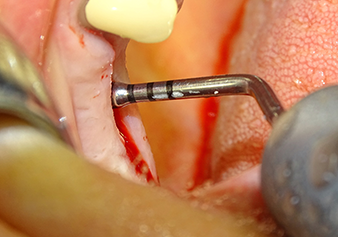

The Schneiderian membrane is carefully detached with the Z25P instrument (phase 1)

Fig.3: Following marking of the implant position and initial expansion of the bed, the Schneiderian membrane is carefully detached with the Z25P instrument (phase 1).

The I2A instrument (diameter 2.0 mm) was then used to perforate the sinus floor intermittently and on the smallest scale possible. This special piezosurgical method ensures that the Schneiderian membrane is not damaged. When the Z25P was used, the membrane was already lifted slightly by the coolant supplied via the instrument tip (Fig. 3). The coolant quantity was just 50% in order to avoid high pressure in the implant bed.